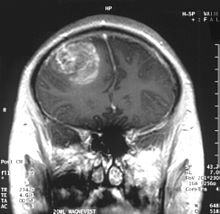

The 80-year-old lawmaker and former Navy pilot, who was re-elected to a sixth Senate term in November, has been recovering at home in Arizona since undergoing surgery at the Mayo Clinic in Phoenix last Friday to remove a blood clot from above his left eye.

Tissue analysis since that procedure revealed that a brain tumor known as a glioblastoma was associated with the clot, his office said. McCain’s doctors said he was recovering from surgery “amazingly well” and that his underlying health was excellent.